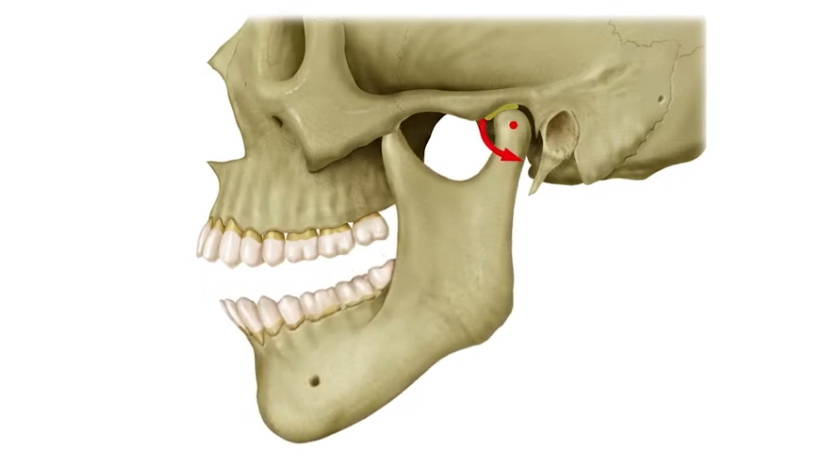

顎関節の運動構造とその重要性

顎の開閉には「回転運動」と「滑走運動」の2種類がある

- 回転運動:下顎が蝶番のように回る(開口の初期)

- 滑走運動:下顎頭が前方に滑る(開口の後半)

- → この2つの動きが合わさることで、大きく口を開けることが可能に

上顎も実は動いている?

口を開けるとき、実は“上顎”もわずかに動いています。

- 開口時、視線が自然と上に向く=上顎が後方へわずかに動く

- 同時に頭部が後屈する(後ろに傾く)

- 視線を動かすために、頭蓋骨全体が微妙に動く必要があるため、結果として上顎も動いている